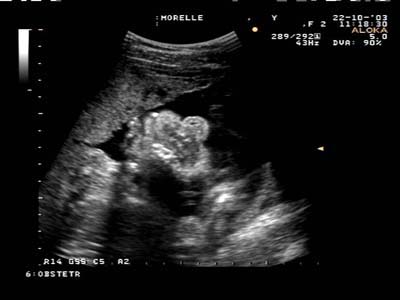

Lèvre supérieure continue